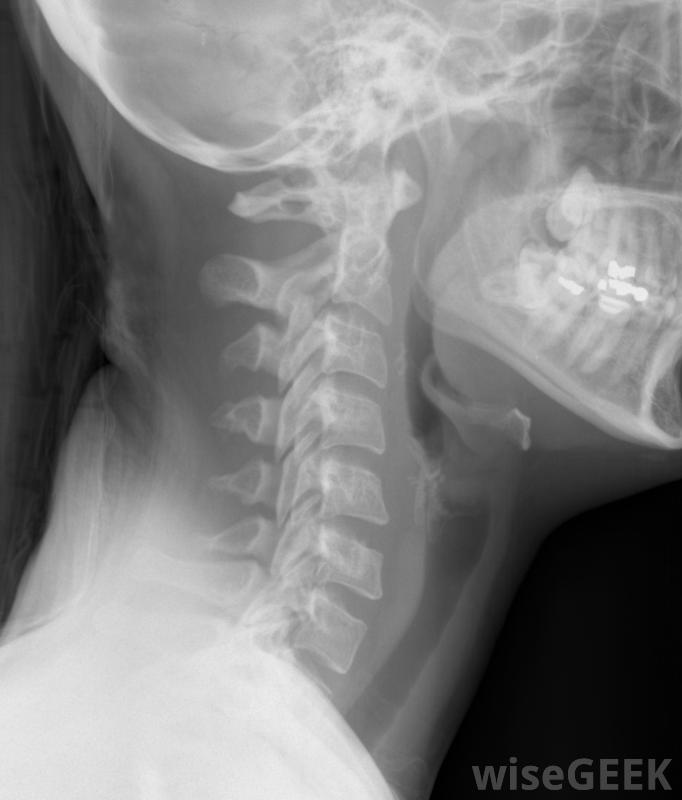

对包括颈椎在内的颈部进行X光检查。

出现颈部疼痛、手部麻木、不稳定或缺乏协调的人可以交由神经外科医生进行评估和可能的颈椎管狭窄症诊断。诊断工具包括核磁共振成像、计算机断层扫描(CT扫描)、神经传导研究、x射线和脊髓造影。根据诊断结果,医生可能首先建议采取保守措施,如物理治疗、减少活动、抗炎药和注射皮质类固醇。如果保守治疗不充分,建议进行手术。